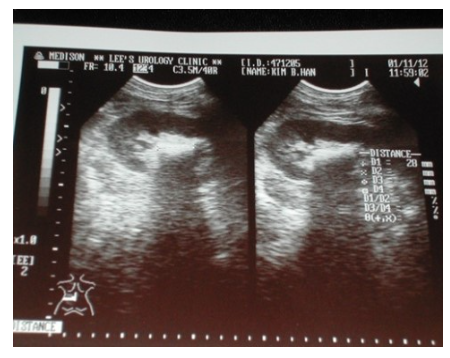

요로결석은 소변이 생성되어 수송, 저장, 배설되는 길(요로)에 결석(돌)이 생긴 것을 말하며 돌이 생기는 곳에 따라 신장 결석, 요관 결석, 방광 결석, 요도 결석 등으로 나뉩니다.

요로계에 결석이 생성되어 소변의 흐름에 장애가 초래되고, 그 결과 극심한 통증이 발생하거나 요로 감염, 수신증, 신부전 등이 나타나는 질환입니다.